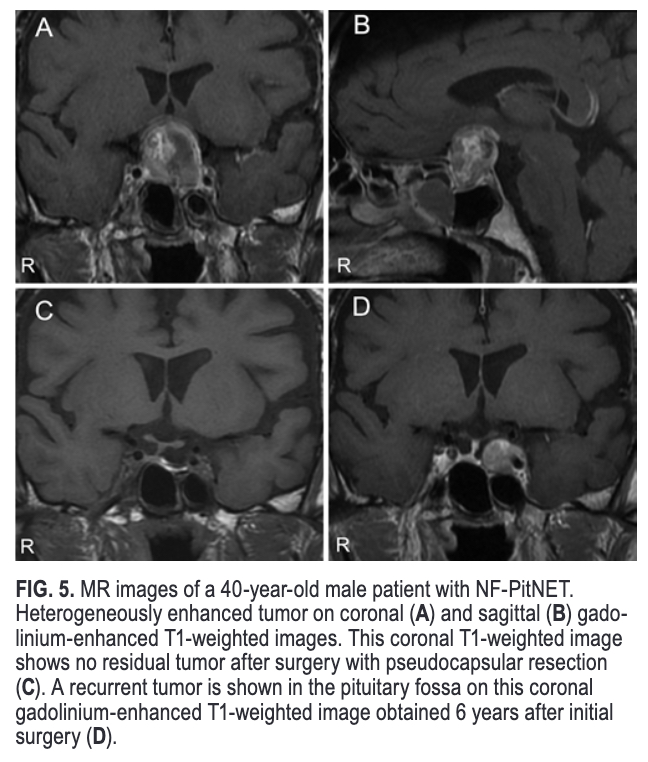

#OnlineFirst: Pseudocapsular resection to prevent recurrence in nonfunctioning pituitary neuroendocrine tumors: a retrospective, single-center study with more than 5 years of follow-up. thejns.org/view/journals/….

#OnlineFirst: Pseudocapsular resection to prevent recurrence in nonfunctioning pituitary neuroendocrine tumors: a retrospective, single-center study with more than 5 years of follow-up.

thejns.org/view/journals/….